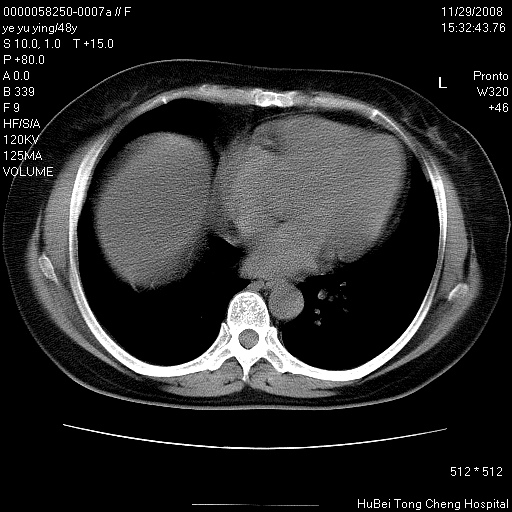

以下是引用zsl6918在2008-11-29 21:47:00的发言:[br]恶性肿瘤病史,转移瘤首先考虑。脂肪肝,胆囊结石。

以下是引用huenhao在2008-11-29 22:11:00的发言:[br]脂肪肝,胆囊结石。左肺病灶建议定期复查。

以下是引用liuyue在2008-11-30 5:44:00的发言:[br]1.左肺病变,首先考虑感染性病变,转移待排;建议治疗后复查。[br]2.肝脏密度普遍减低,考虑与化疗有关。[br]3.胆囊结石.